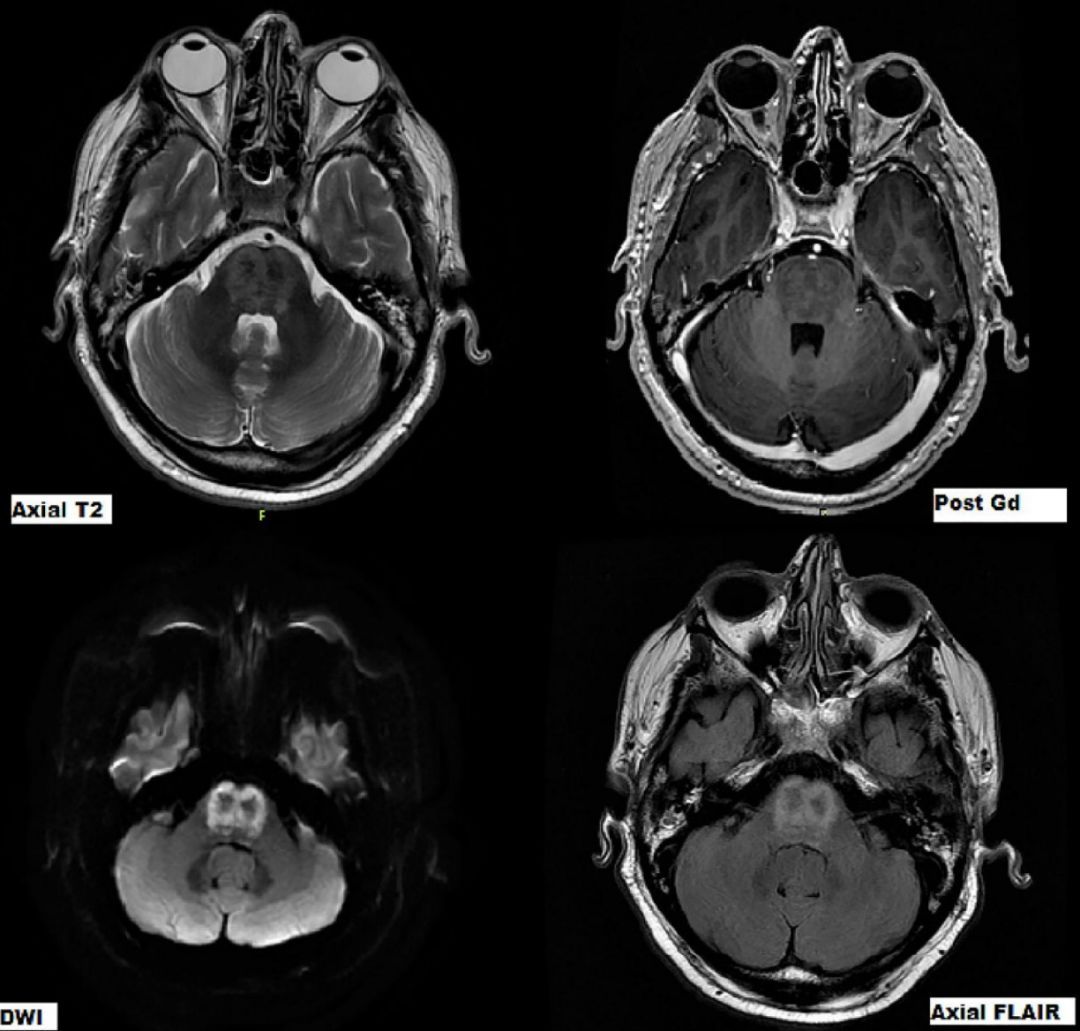

59岁,男性,急性高热伴视物模糊就诊。查体:左眼视力下降,部分左上睑下垂,左侧轻偏瘫。病情进行性加重,逐渐出现嗜睡、呼吸衰竭、进行性延髓麻痹和自主神经功能障碍(多汗、流涎、心动过速、高血压)。48h后出现面部及四肢无力、反射减弱,转入重症监护室。

4周时MRI:

答案:脑干脑炎与戊型肝炎并发急性多发性神经病。

脑脊液检查:WBC:20*106/L,蛋白1.6g/L,病毒和细菌均阴性。莱姆病、血液传播病毒、梅毒、自身抗体阴性。神经传导提示明显的周围神经受累,急性运动和感觉轴突神经病变。接受了脑干脑炎和格林巴利综合征的感染性和炎症性治疗。完善脑脊液戊肝病毒(HEV)RNA阳性。经过治疗后好转出院。脑干脑炎的病因大致分为:①感染性:李斯特菌、肠道病毒或单纯疱疹病毒感染等;②自身免疫性:多发性硬化、白塞病;③肿瘤和(或)副肿瘤性:与抗Yo抗体和抗Tr抗体相关的副肿瘤综合征。其他罕见的病因包括:JC 病毒感染、CLIPPERS 综合征、淋巴瘤、亚急性硬化性全脑炎等。